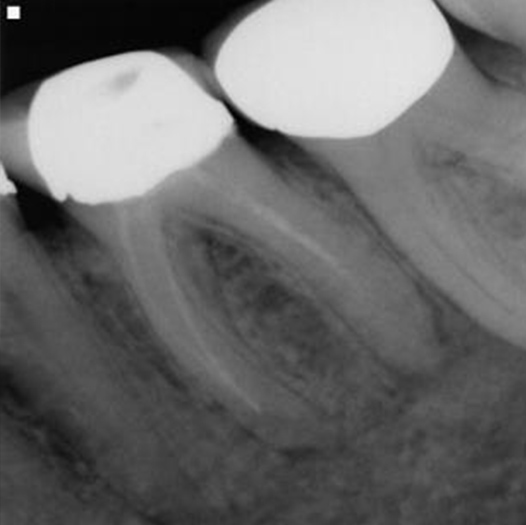

Before

After

Before Root Canal treatment

After Root Canal treatment